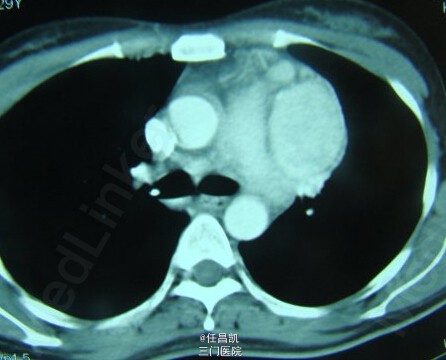

患者女,30岁,因胸闷不适4个月就诊,先后疑诊为肺癌、肺结核等治疗效果欠佳,进入我院。患者发病以来,无发热、咳嗽、血痰、胸痛等。

查体:心肺听诊无异,未见阳性体征。 辅查:CT如图所示。

入院诊断:肺部肿块待查 处理:入院后行手术探查+切除术治疗,术中快速病理检查排除恶性肿瘤,切除病灶,病理和免疫组织化学检查诊断为巨大淋巴结增生症。术后予补液、营养支持等对症处理,患者恢复顺利,复查CT无异,症状缓解遂出院。 出院诊断:胸内Castleman病